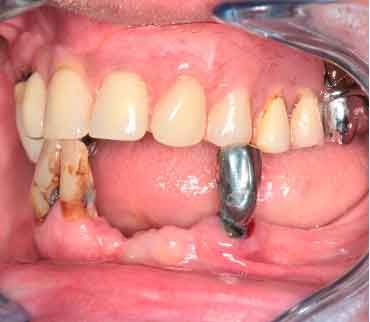

The periodontal structures of the remaining teeth are no longer sufficient. An edentulism is considered. The treatment plan is directed towards a removable maxillary complete prosthesis and an implant-supported mandibular complete prosthesis.

In a typical digital workflow, the first step involves intraoral scanner (IOS) acquisition. However, in cases with insufficient references, obtaining an accurate bite can be challenging. Discover alternative methods to construct dynamic virtual patients, bridging the gap from initial situations to provisional solutions.

3D models - Bite scan from intra-oral scanner

When traditional IOS scans lack necessary references, Cone Beam Computed Tomography (CBCT) data serves as a possible alternative. By utilizing CBCT scans, clinicians can establish accurate reference positions for treatment planning.